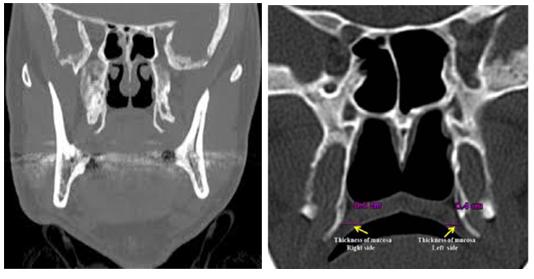

翼钩是在口腔上腭两侧的蝶骨翼内板的小突起,为腭帆张肌勾绕。正常人一般突起不明显,如果长期腭帆张肌紧张,致使翼钩发生退行性病变,刺激咽舌部神经等引起疼痛;或由于翼钩过长和滑囊炎症引起相应部位疼痛。

本病一般多为单侧发病,阵发性或持续性腭咽部疼痛,吞咽时诱发或加重,部分患者或伴有咽喉异物感或不适,颞颈部酸痛或不适。在局部可见明显的突起或触压痛,这种疾病没有经验的医师往往被误诊为慢性咽炎等,所以很多患者常反复多次就医,或以咽喉炎长期治疗而不见效果。

因此,该病应与舌咽神经痛、茎突综合症、咽喉局部的炎症等相鉴别。首选手术治疗,次选局部封闭治疗。经过手术治疗的翼钩过长患者大多可以获得明显的疗效,很少复发。一般预后良好。